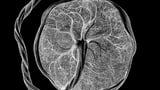

A comprehensive, spatially resolved atlas maps the human maternal–fetal interface across gestation, integrating multiomics and spatial transcriptomics to illuminate regulatory networks, cellular dynamics, and placental architecture.

A 0.5-micron-resolution Stereo-seq atlas maps 1.1 million cells across 16 basal plate sections, revealing six spatial communities that map to decidual, vascular, maternal–fetal junction, and floating villus regions.

Using high-resolution single-nucleus multiomics and spatial mapping, the study identifies cell types, regulatory networks, spatial niches, and dynamic processes driving placental development and its complications.